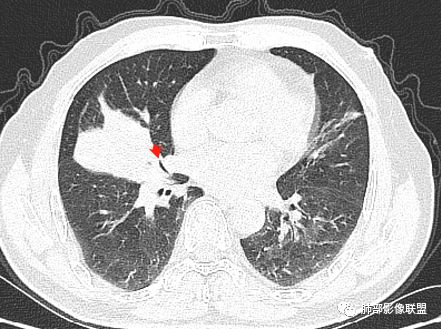

主病灶在中叶,但是左肺舌段叶有条索影,陈旧病变。蓝色箭头支气管受压,是淋巴结肿大

主病灶在中叶,但是还有结节状病变在下叶

这个支气管是走形通畅,但是壁增厚的。比较符合炎症改变

内侧段是通畅但是受压的

外侧段一开始狭窄

但是远端通畅,所以我认为支气管都没有堵塞,不太可能是鳞癌

边缘还有多发小灶

淋巴结肿大,钙化。

病灶明显平直,中央是粘液栓,低密度,分界清楚

综上,考虑炎症,结核。